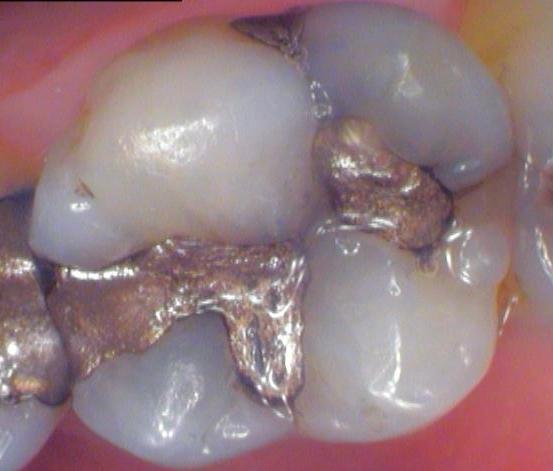

Ceramic Crown

This patient had an old and failing metal filling, and there were visible cracks on her back molar. She wanted to restore the tooth with something that looked natural, so a ceramic crown was chosen. These types of restorations are both strong and beautiful.